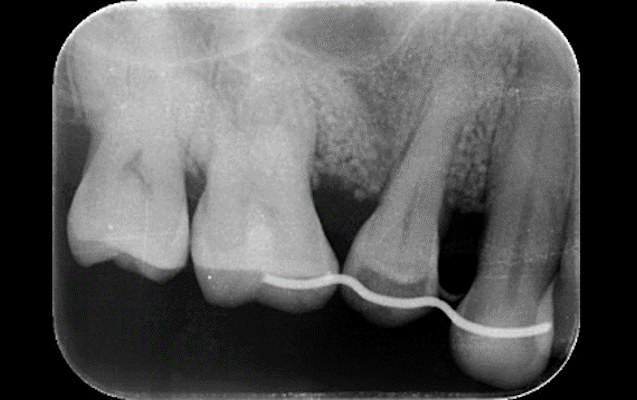

また、根本的な治療のために、主訴部位だけでなく口腔内全体の状態を把握する必要があります。そのために当院では口腔内全体のデジタルレントゲン撮影を行います。

昨今では重度歯周病に対する治療の研究が進み、現在では歯周病により溶けた歯槽骨の再生が可能となっています。根の先端を超えるような骨吸収が起きていたとしても残すことができるとの報告もあります。

難易度の高い治療ではありますが、歯科用CTによる正確な診断、マイクロスコープを用いた精密な治療により可能となります。